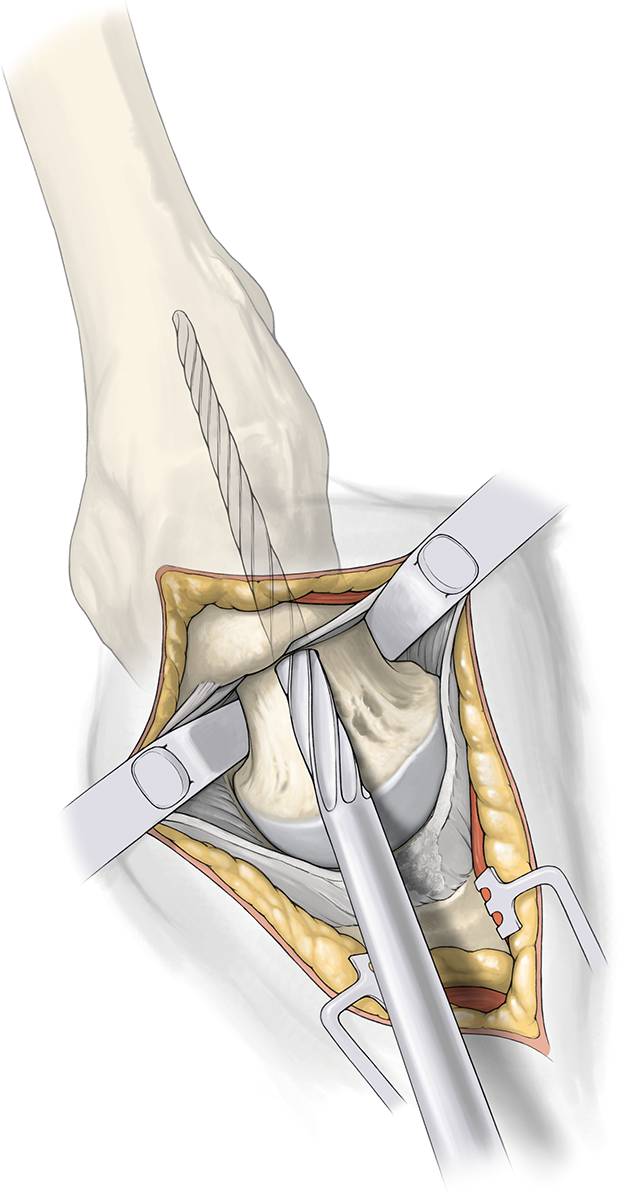

Fig. 4

Intracapsular preparation. Capsular incision is made in line with the skin and the femoral neck with an electrocautery. Free the lateral border of the acetabulum 1 cm anterior und posterior. Remove a part of the labrum. Hemostasis is important at the basis of the capsule. Replace the sharp elevators with blunt Hohmann around the neck first posterior then anterior. Identify the saddle of femoral neck (green line in Fig. 7)